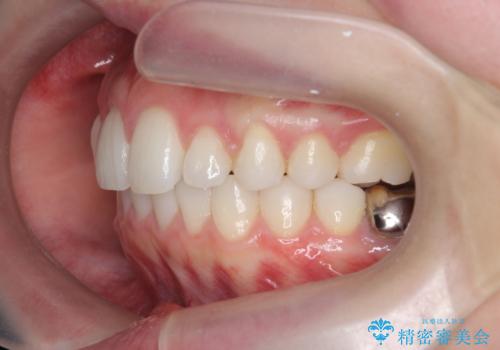

前歯が引っ込んでいると、そこが影になり大変目立ちます。

矯正治療で大きく見た目を改善することが可能です。